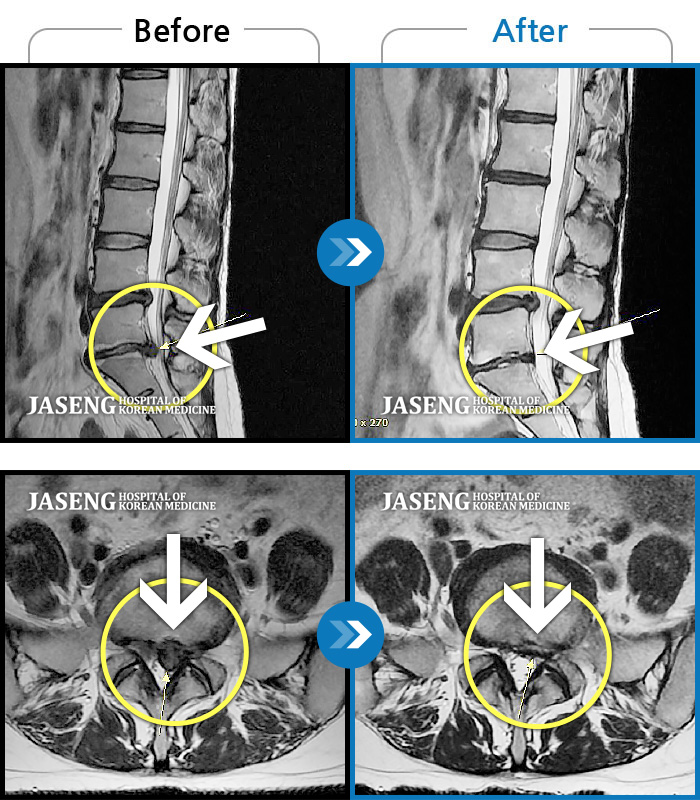

허리디스크

울산 · 정운석 원장

하요추부 통증과 양측 대퇴부 후면 저림

촬영시기

2020.01.10 ~ 2022.08.20

2022.08.26